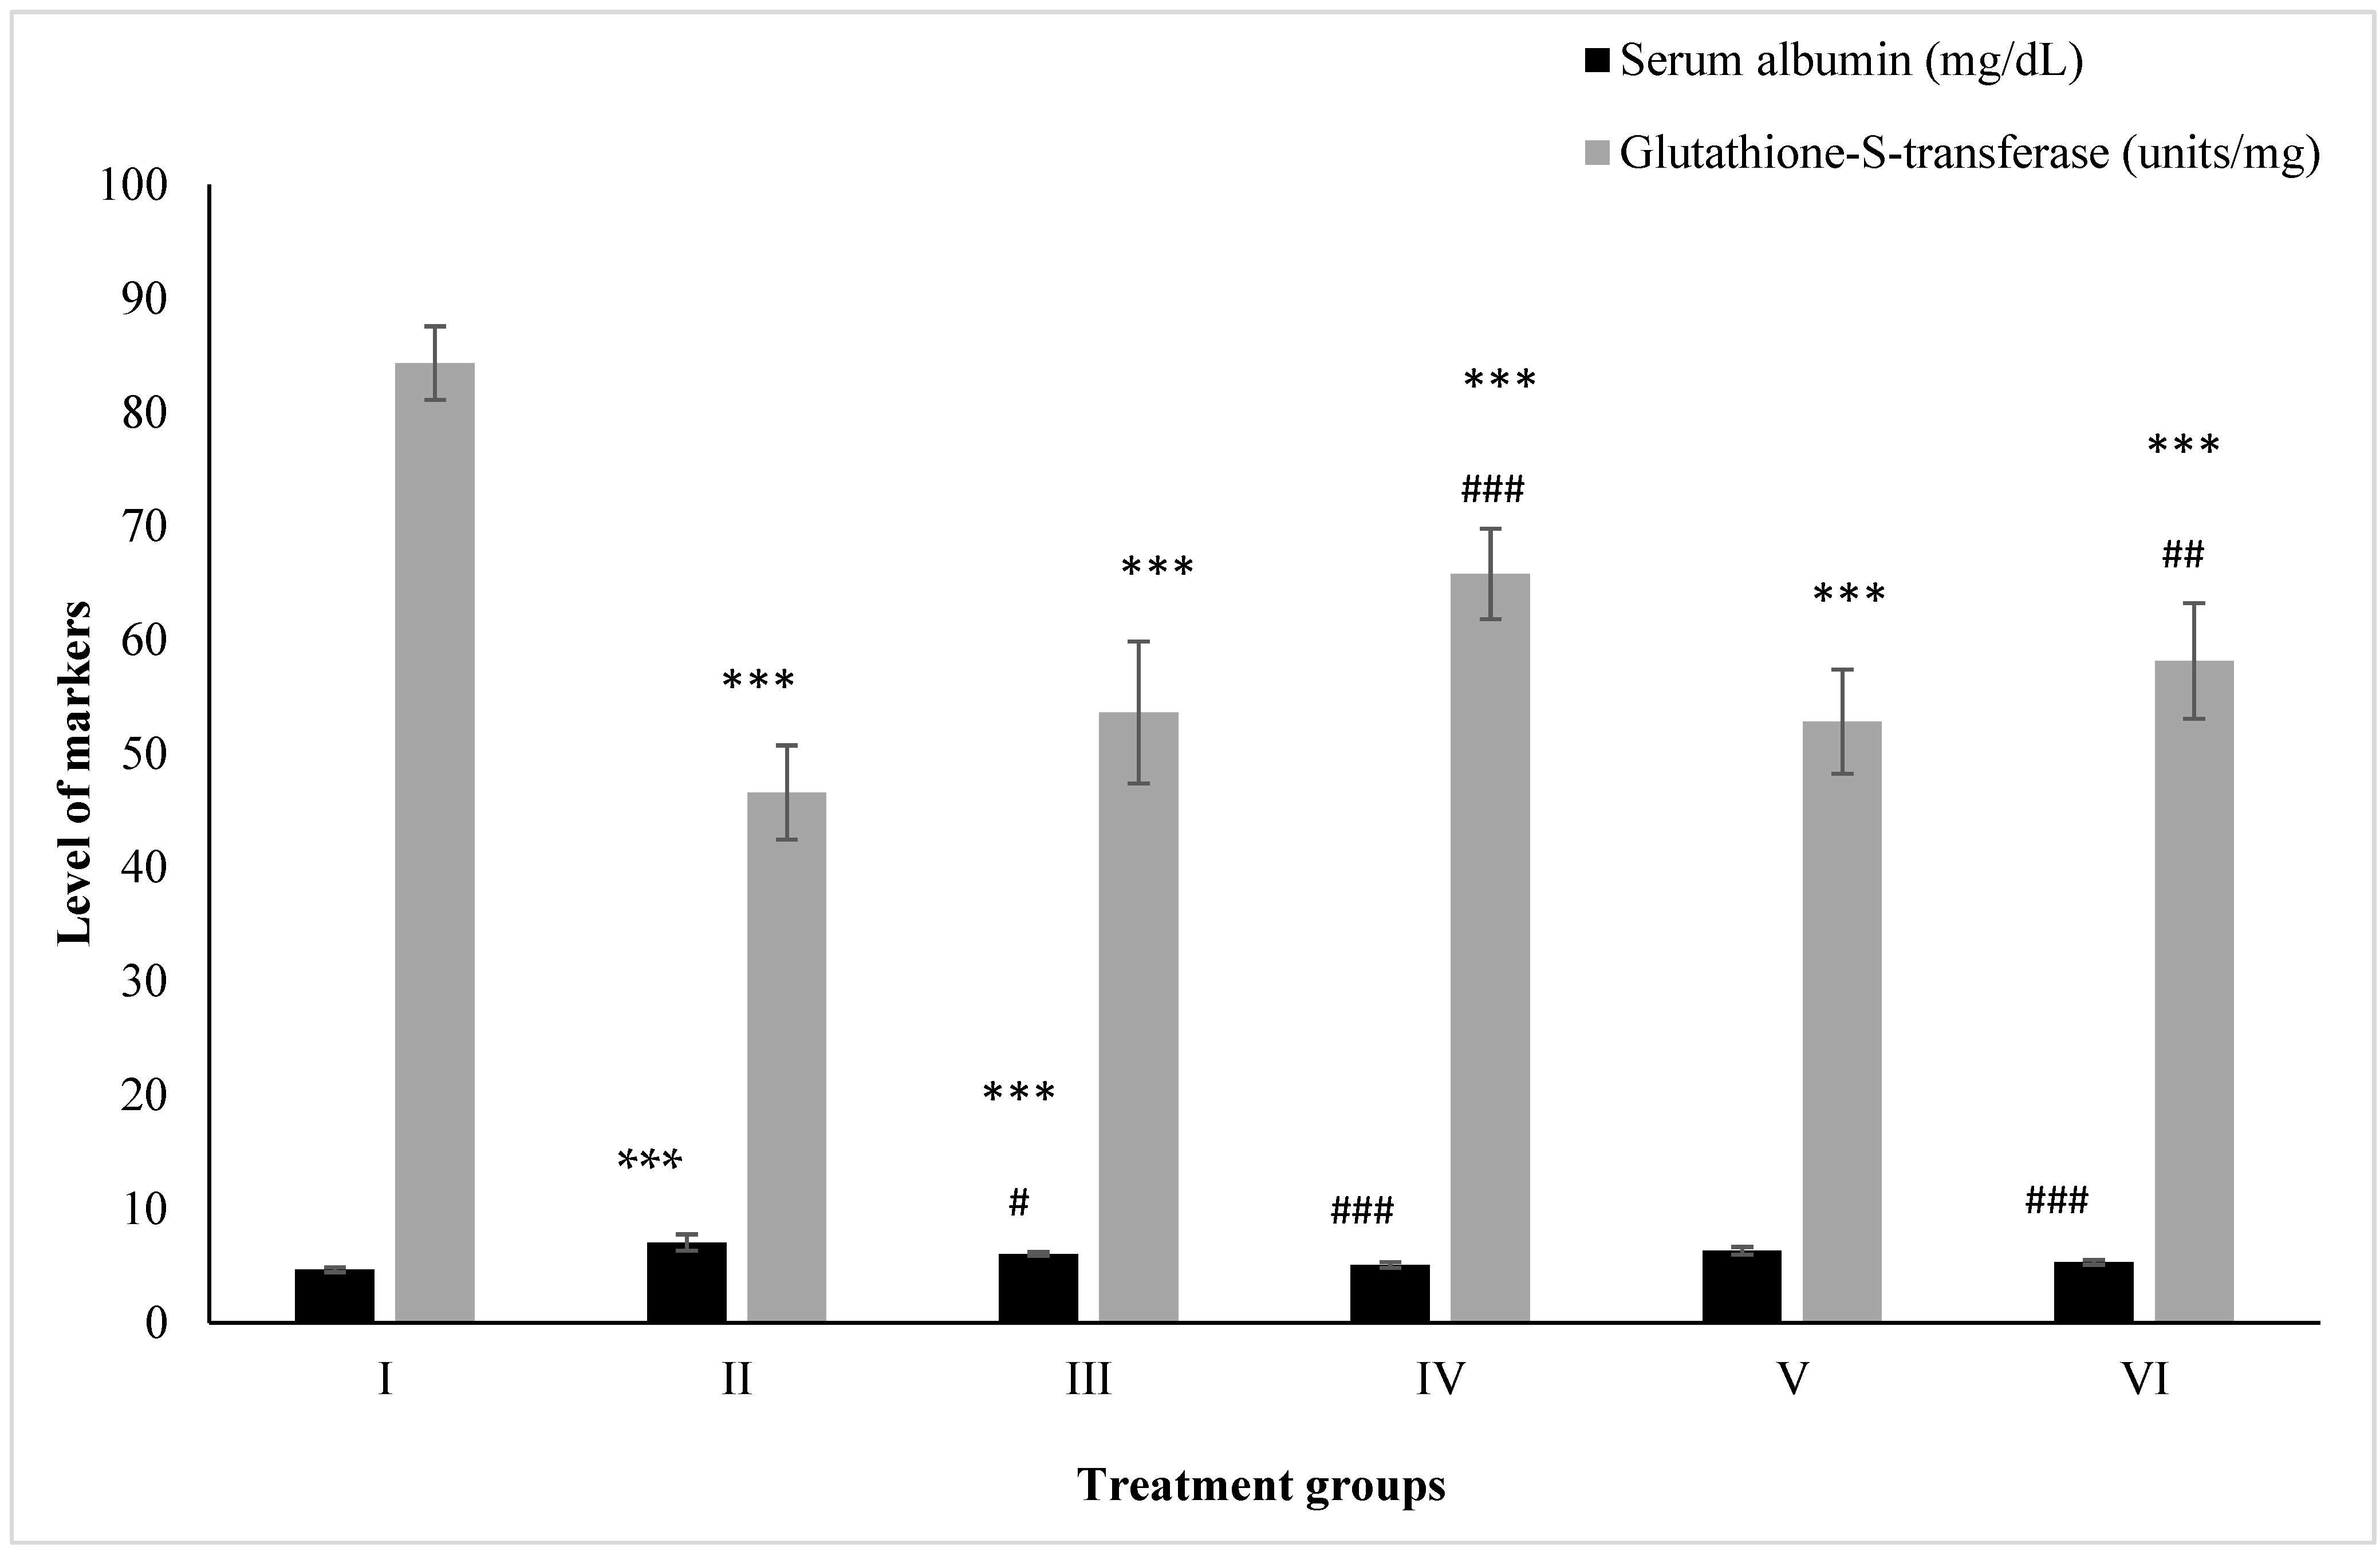

2.3. Effect on Kidney Toxicity Markers

2.3.1. Albumin

2.3.2. Glutathione-S-Transferase